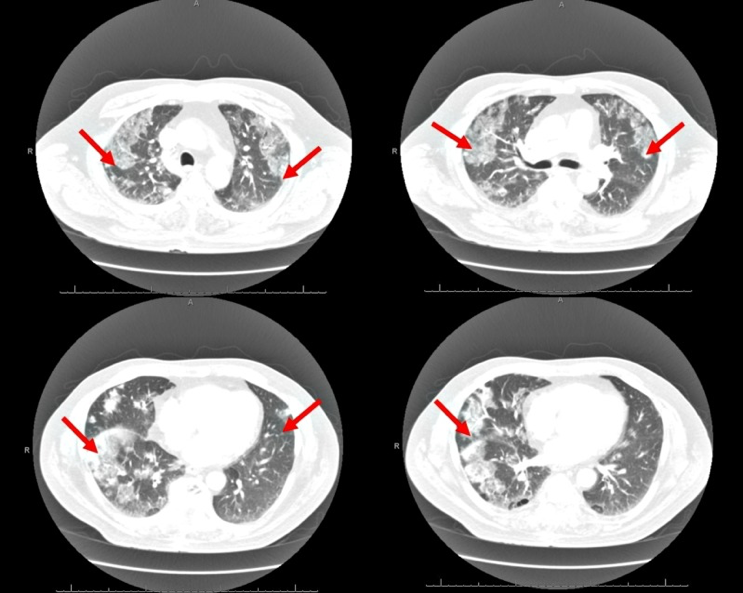

(6/10) DAP-induced eosinophilic PNA (AEP) should be suspected with DAP exposure + >25% eosinophils in bronch +🌡️ fever + 😮💨 dyspnea + new diffuse bilateral infiltrates on CT/CXR. ncbi.nlm.nih.gov